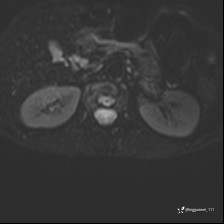

病例女,39岁,腰痛来诊,只有CT可能要鉴别诊断,而MR可以定性吗?

患者性别:女

患者年龄:39岁

主诉:腰痛

DWI ADC